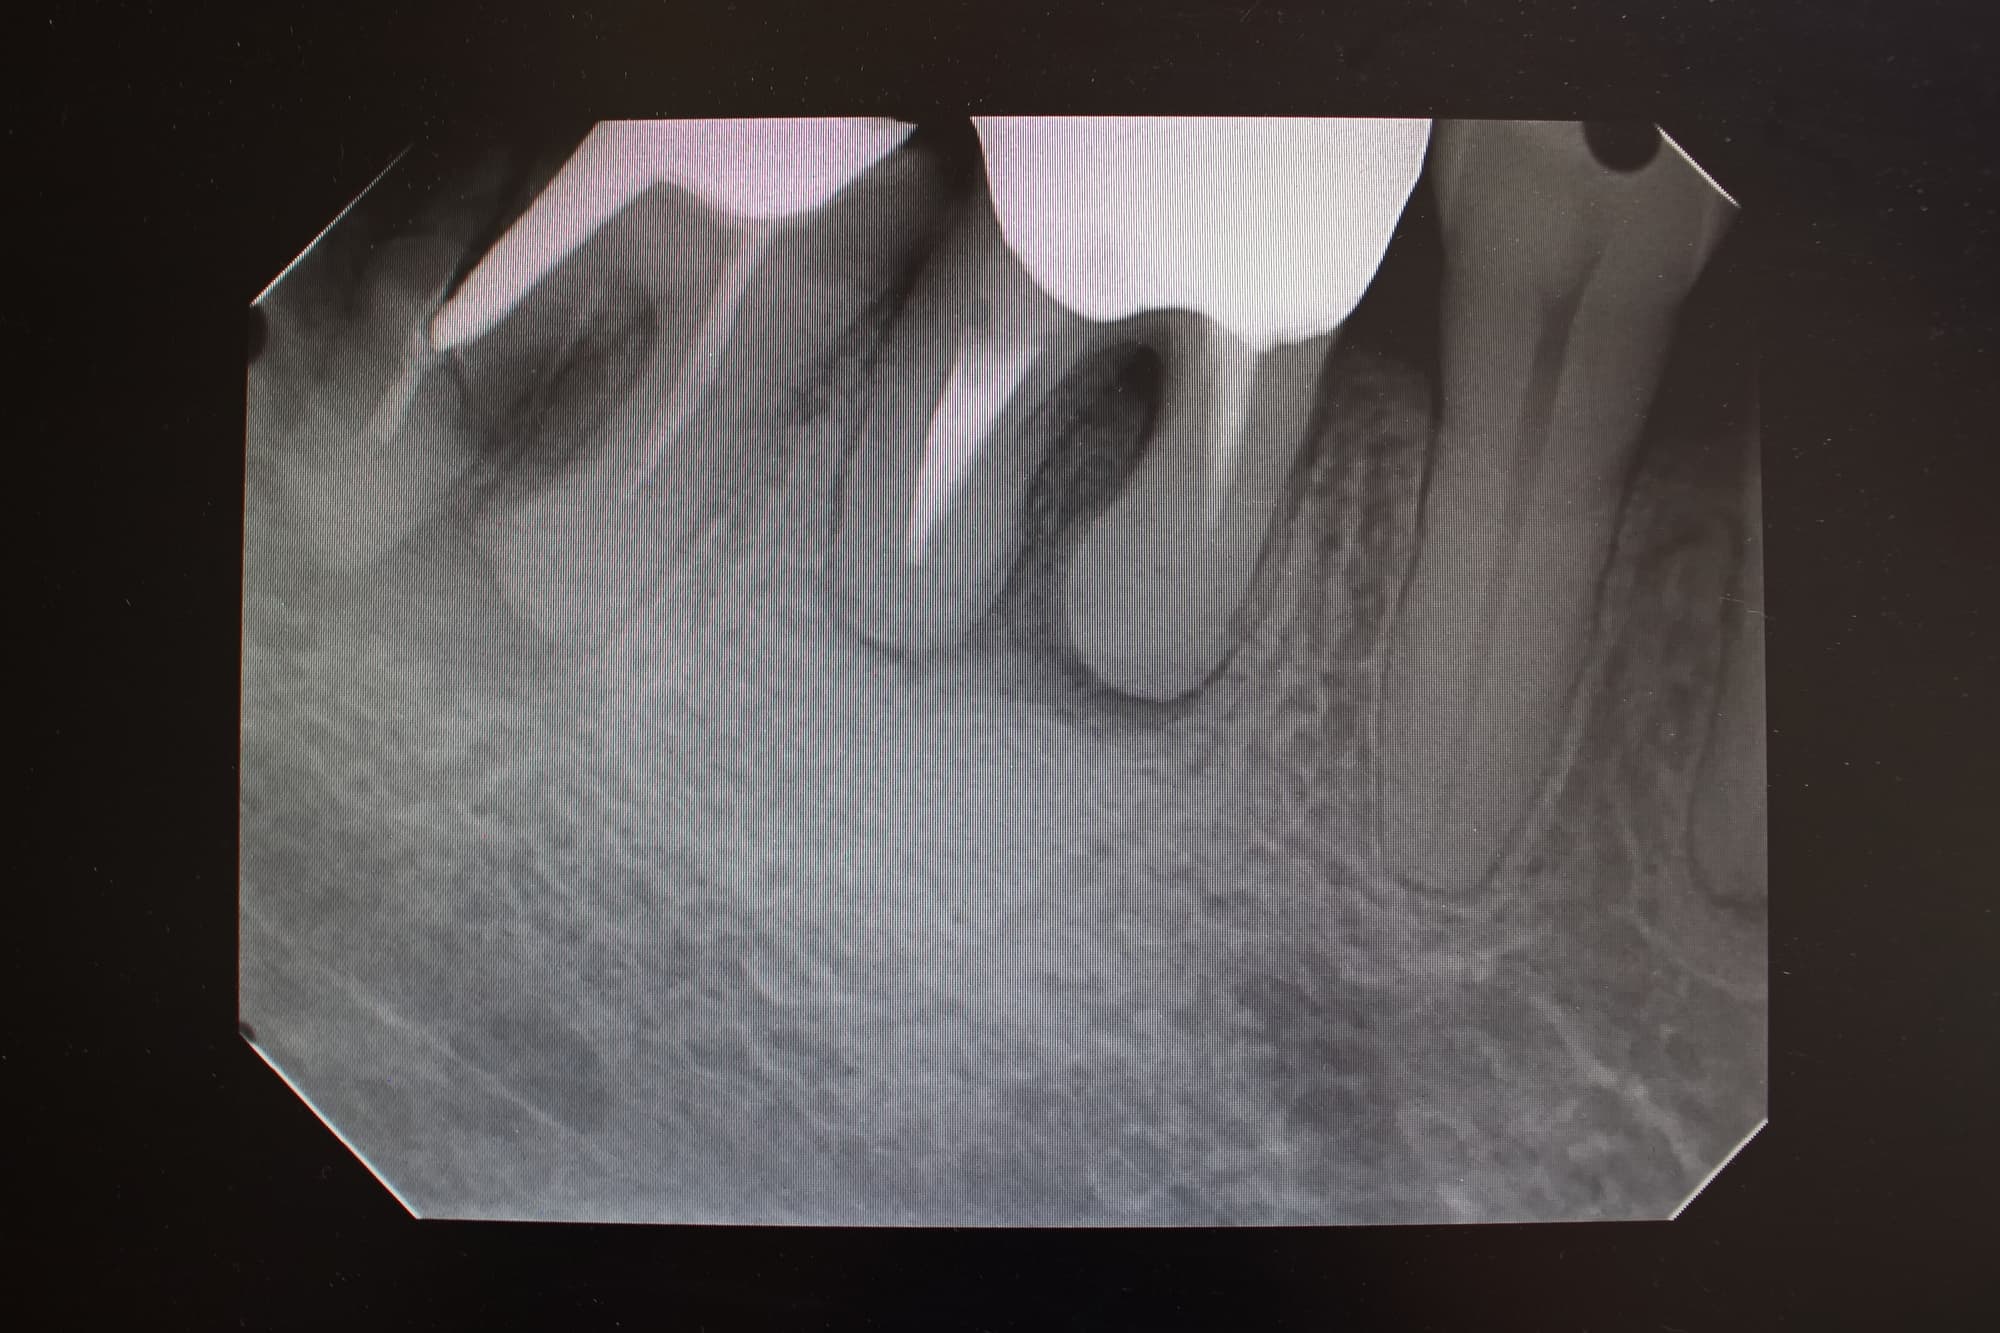

まず重要なのが正確な診断です。レントゲン撮影やCT検査を通じて、虫歯の進行状態や根管内の感染の程度を把握します。診断結果をもとに、治療方針を決めていきます。